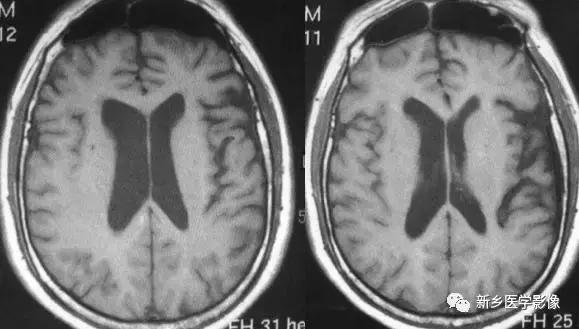

1.普遍性脑萎缩

普遍性脑萎缩常同时累及灰质和白质.可表现有双侧侧脑室扩大。而且是双侧侧脑室轻度对称性扩大最常见的原因。尤其是以脑白质萎缩为主的病人。

普遍性脑萎缩引起的侧脑室扩大通常比较对称.中线无移位。其特点是同时有脑沟、脑裂增宽等脑皮质萎缩的表现.

普遍性脑萎缩可见于正常老年人

原因有:①与年龄有关的脑萎缩CT和MR检查可见脑室、脑池轻度扩大.脑沟轻度增宽.常以额叶和镰旁更明显。②阿尔茨海默病本病除具有普遍性脑萎缩的一般表现外.颞叶萎缩常很明显且现较早,故侧脑室扩大以颞角更明显。阿尔茨海默病神经元丧失的严重程度从重到轻依次为海马、颞叶后部、额叶和顶叶。③Huntington‘s病(舞蹈症)是一种常染色体显性遗传的基底节和大脑皮层变性性疾病。主要损害基底节和大脑皮层,尾状核、壳核病变最明显。小神经节细胞严重破坏,大细胞也减少、尼氏体消失、核固缩、出现类淀粉小体,还有脱髓鞘改变和胶质增生,基底节部受累常最明显且发生最早。临床主要根据3大特征:舞蹈样动作、痴呆、家族史。④帕金森病又称震颤性,是一种常见的锥体外系疾病。临床以震颤、肌强直和运动障碍特征。震颤喂首发症状,休息和安静时明显。CT除有萎缩外,有时可见基底节钙化。MR T2WI上基底节区和脑白质内常有多发高信号斑点存在⑤匹克病(Pick’s disease)又称脑叶硬化症女性多见,50岁为发病高峰,临床以进行性痴呆为主要表现。CT和MR常以额叶和颞叶萎缩为主。另一特点,双侧萎缩常不一致,左侧较明显,颞上回的前半部萎缩,而后部常正常。⑥Jakob-Creutzfeldt’s病一种以迅速进行性痴呆为特点的脑病CT和MR表现为侧脑室对称性扩大,脑沟脑裂增宽。短期复查可见萎缩程度明显加重,晚期可出现脑白质弥漫性脱髓鞘改变。⑦其他原因如缺氧、中毒、物理损伤、营养不良等。